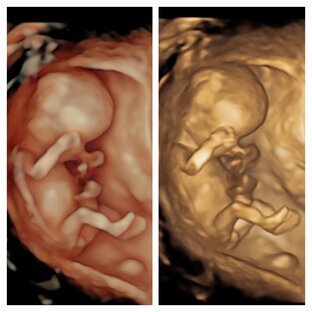

ТИХИЕ УБИЙЦЫ. ⠀ ☑️ И снова амниотические тяжи. ⠀ ⠀ ☑️ Здесь история не простая. Суррогатное материнство - вынашивание и рождение женщиной ребёнка для другого лица или лиц, которые станут родителями ребёнка после его рождения 🤰🏻 ⠀ ☑️ В 13 недель беременности сердцебиение не определялась. На этом исследование можно было и закончить, но это не в моих правилах. ⠀ ☑️ Были обнаружены амниотические тяжи, которые пережимали пуповину и не оставили нам шансов для спасения малыша. ⠀ ☑️ Амниотический тяжи частично фиксировали стопы, но это можно было бы поправить в более позднем сроке. ⠀ ☑️ Два года назад у этой же пациентке была похожая ситуация: определялась двусторонняя косолапость. Визуализировался разрыв амниотических оболочек с образованием тяжей. В тяжи вовлечены нижние и верхние конечности. ⠀ ☑️ Если Вам поставили диагноз неразвивающаяся беременность, то лучше провести детальное УЗИ, иногда это даёт очень ценную информацию для планирования последующих беременностей.

В последнее время огромное количество людей приходят узнать пол своего малыша. ⠀ ✅ В моей клинике - это не только узнать пол. ⠀ ✅ Это ещё осмотр и демонстрация. ⠀ ✅ Это исследование не заменяет скрининг! ⠀ ✅ Фото в подарок. ⠀ ✅ Берегите себя. ⠀ ☑️ Здесь расщелина верхней губы (заячья губа). ⠀ #саренко